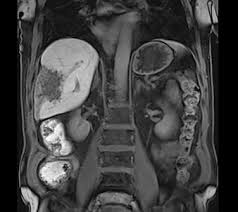

The Use Of Whole Body Mri In Multiple Myeloma Rcp Journals

The Use Of Whole Body Mri In Multiple Myeloma Rcp Journals from www.rcpjournals.org

Multiple myeloma is a cancer of plasma cells, which are white blood cells found mainly in the bone marrow. Find more information on clinical trials that are open for enrollment at mount sinai's center for excellence for multiple myeloma. Multiple myeloma (mm), also known as plasma cell myeloma and simply myeloma, is a cancer of plasma cells, a type of white blood cell that normally produces antibodies. Treatment response, detection of relapse. Related online courses on physioplus. 16,000 new cases and 11,000 deaths. Changing the treatment landscape for hematologic malignancies learn more. In multiple myeloma, when the cancer protein level is up, the normal antibody levels are down. If you still can't find it, please let us know so we can add it!. Tell the radiologist or the radiology technician about your diagnosis before receiving dye injection into. It accounts for approximately 10% of all. Other tests include blood monoclonal immunoglobulin and radiology tests to determine the extent of bone lesions. Spotlight revised international staging system for multiple myeloma: